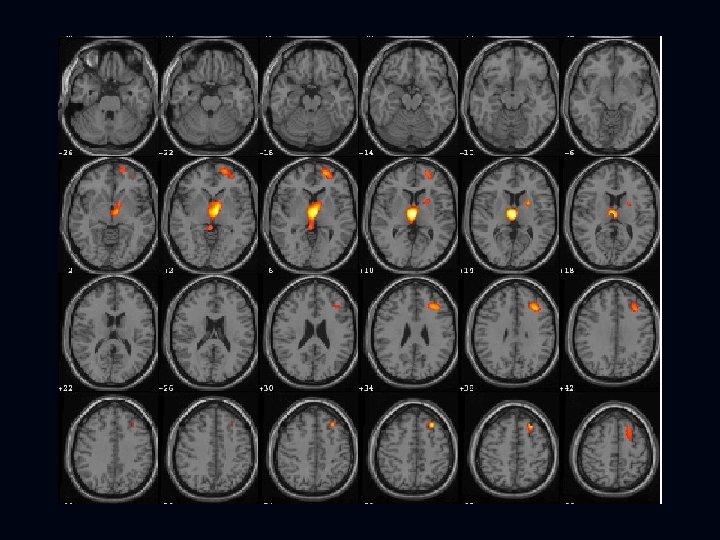

EDC SPECT of Case 1